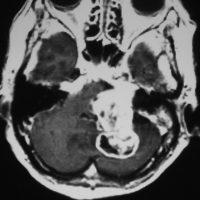

典型的な例1

舌萎縮(舌が右側に曲がっている)に気づいて発見された舌下神経鞘腫です。

舌の右側だけが痩せて萎縮しています,前に出すと麻痺側に曲がります。

舌に波のようなシワができます。

頭蓋底の舌下神経管から頭蓋底部,深頸部に伸びた6cmくらいある大きな舌下神経鞘腫です。舌萎縮以外の症状がないので,手術しないで何年も経過観察していますが大きさは変わりません。右側の画像では内頸動脈が圧迫されていますが,狭窄して血流が悪くなるようなことはありません。